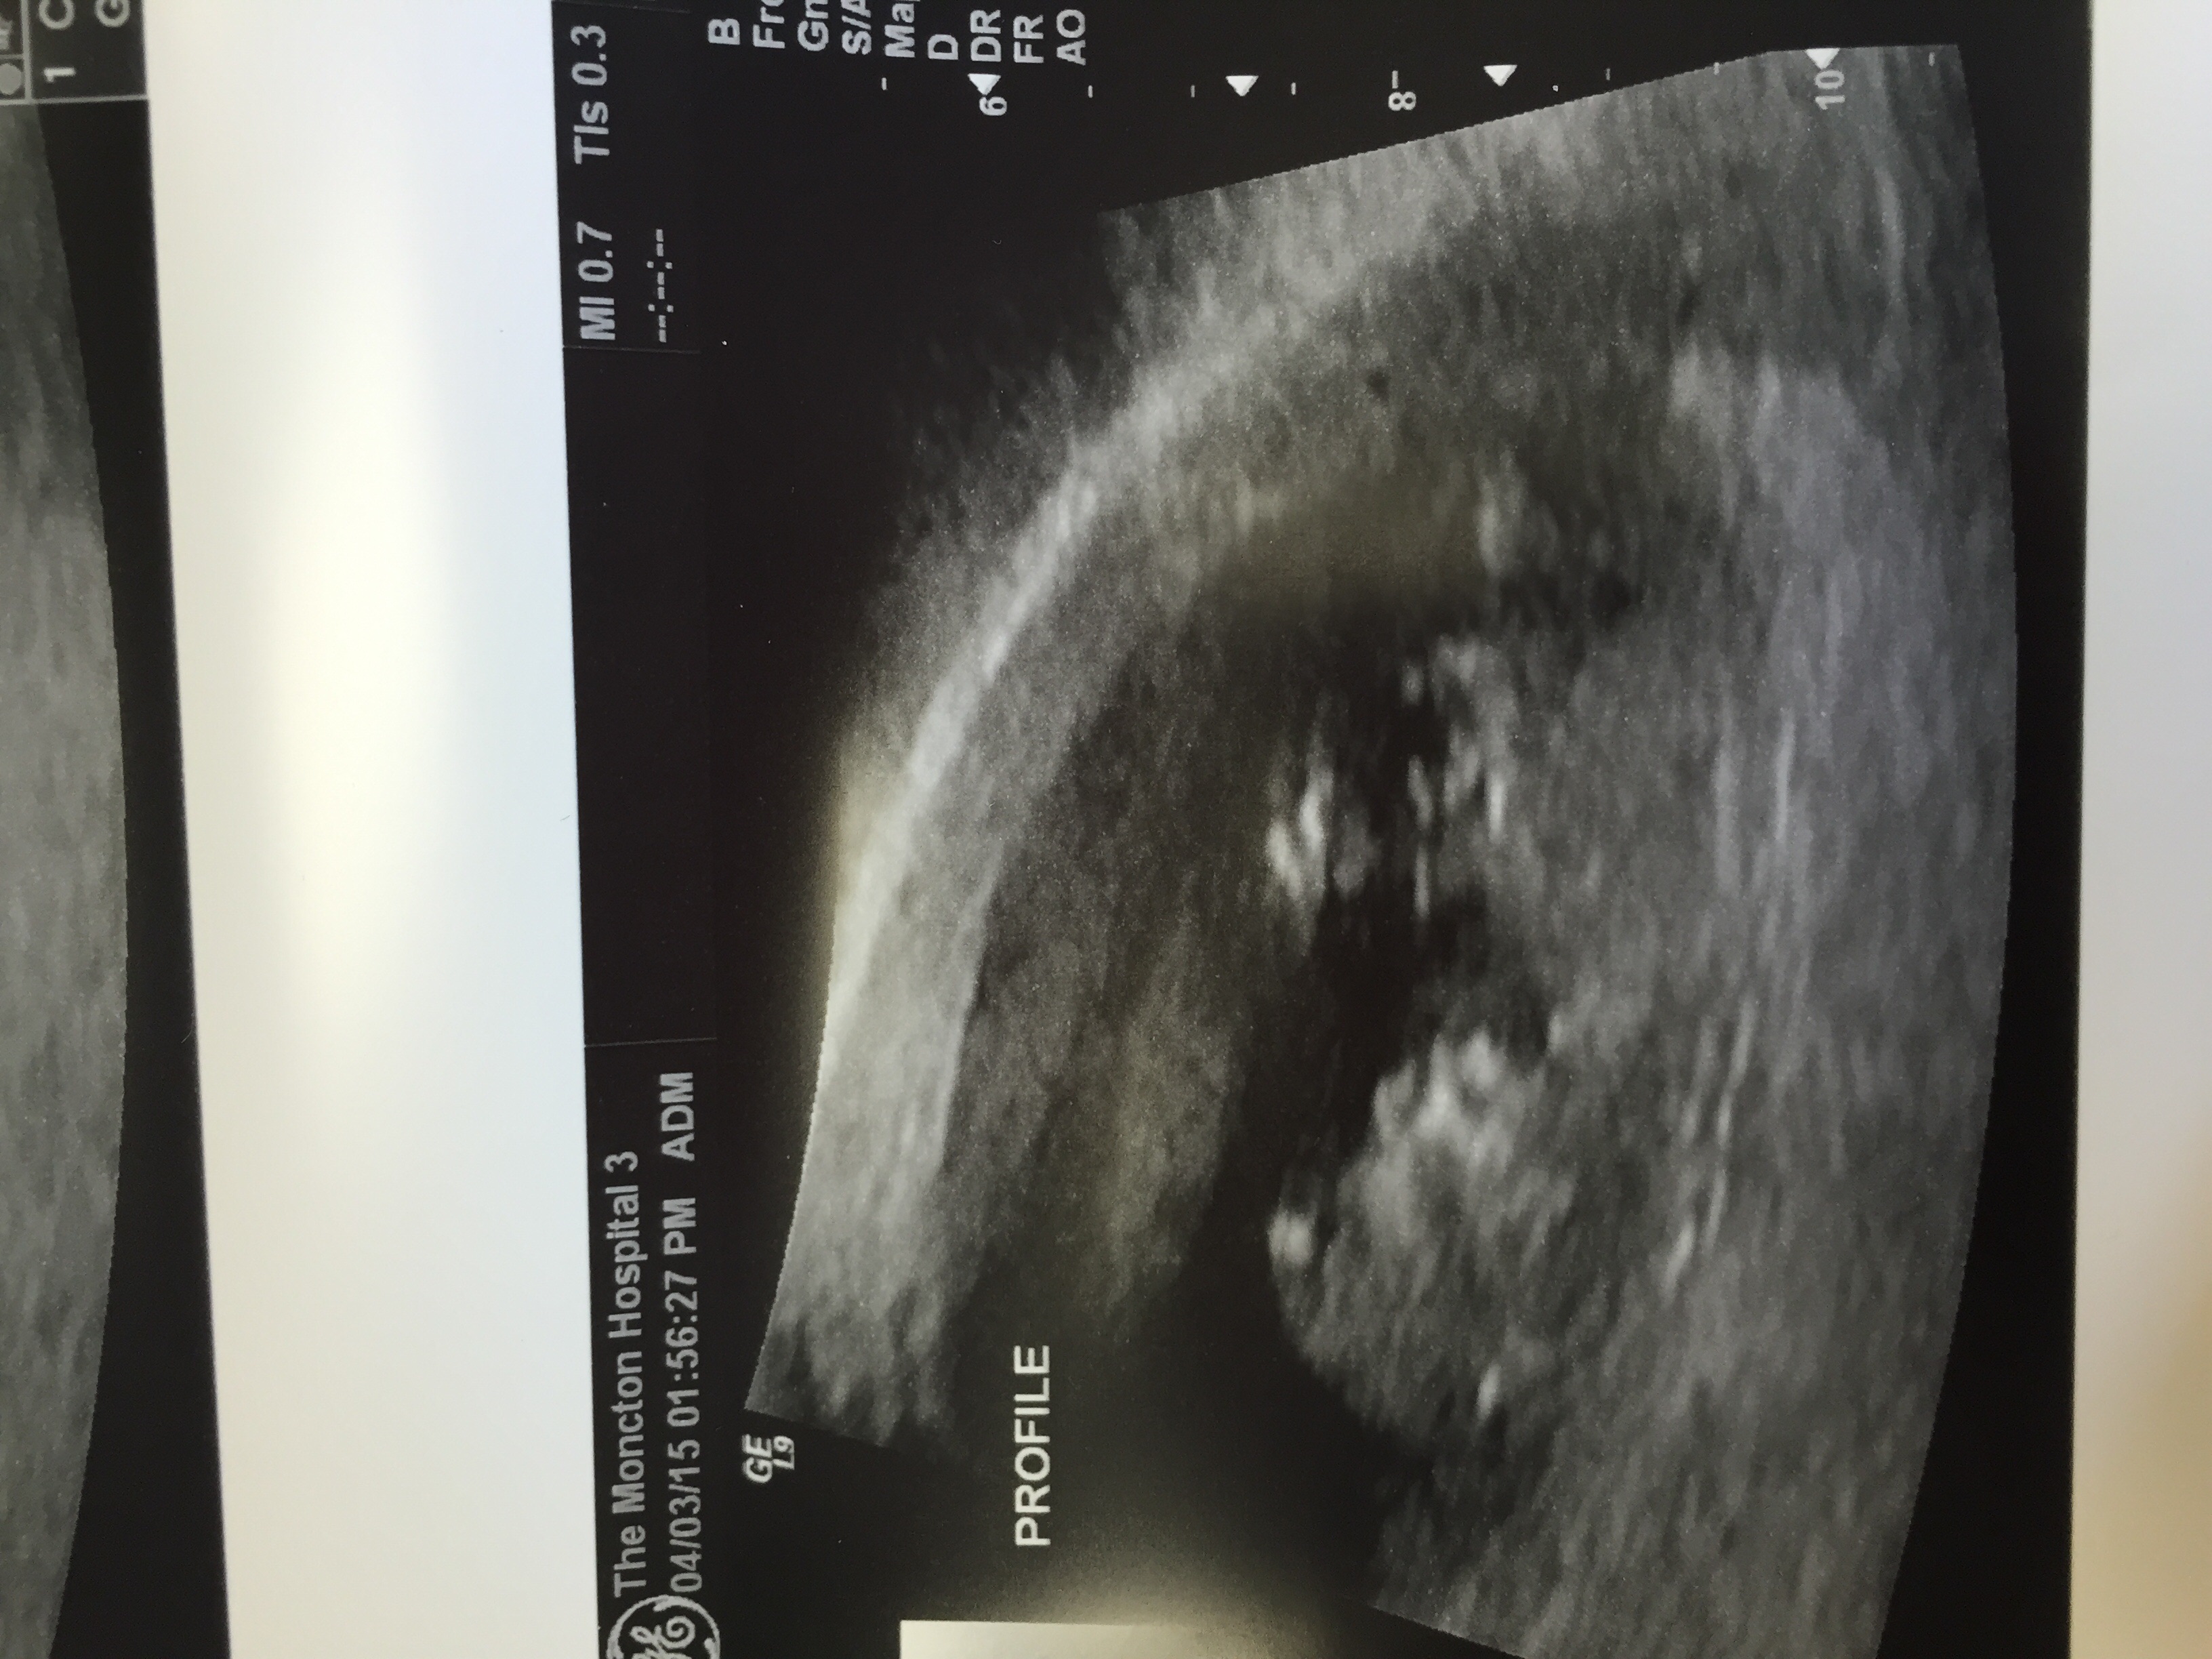

Re: anyone want me to guess gender with Ramzi theory?